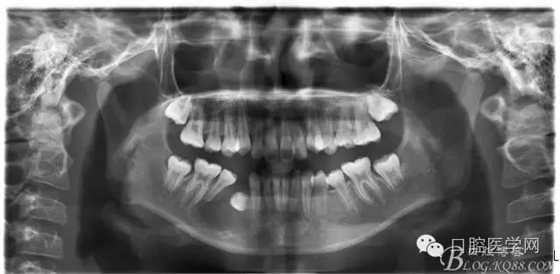

術(shù)后一個月 三個月 五個月 八個月 拔除第一雙尖牙后曲斷片:

正畸查:替牙合。第一恒磨牙中性合。上牙弓尖圓型下牙弓方圓型。前牙覆合3度覆蓋7.5mm。下前牙咬到上舌側(cè)牙齦。上頜擁擠4.0mm,下頜擁擠

3.0mm。上頜稍前突下頜后縮,上下唇前突,上前牙覆蓋下唇,下唇外翻。面下三分之一過短,頦唇溝明顯,開唇露齒,頦饜窩明顯。顳下頜關(guān)節(jié)開閉口無彈響,無壓痛,開口型開口度正常。